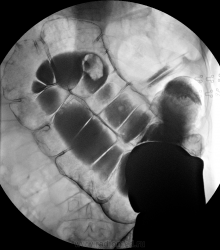

Данная пациентка(60 лет) была направлена к концу недели на исключение органической патологии, могу сказать исследование затянулось до получаса. Газ не вводился, снимки делались без предворительного увеличения.

Пациентка мне показалась интересна в плане демонстрационного случая долихомегаколона сигмовидного отдела ободочной кишки, на самом деле ей проводили и до меня ирригоскопию и ФКС по месту жительства, эндоскопическая картина совпадает с данной рентгенологической, эндоскописты описали "сигму" сравнивая её с мешком. Видно гипотонию и сглаженность гаустрации сигмовидного отдела ободочной кишки, поперечник значительно увеличен, можно отметить удлинение и дополнительный изгиб.

А газ на самом деле не вводился, да и подготовка желает лучшего, восходящий отдел я так и четко не увидел, а мои 400мл рентген-контрастного вещества как капля в море, пришлось ещё 1 литр вводить.

Да кстати, в данном случае можно считать метода была традиционной, 1,5 литра рентген-контрастного вещества, а правые отделы забиты кишечным содержимым.